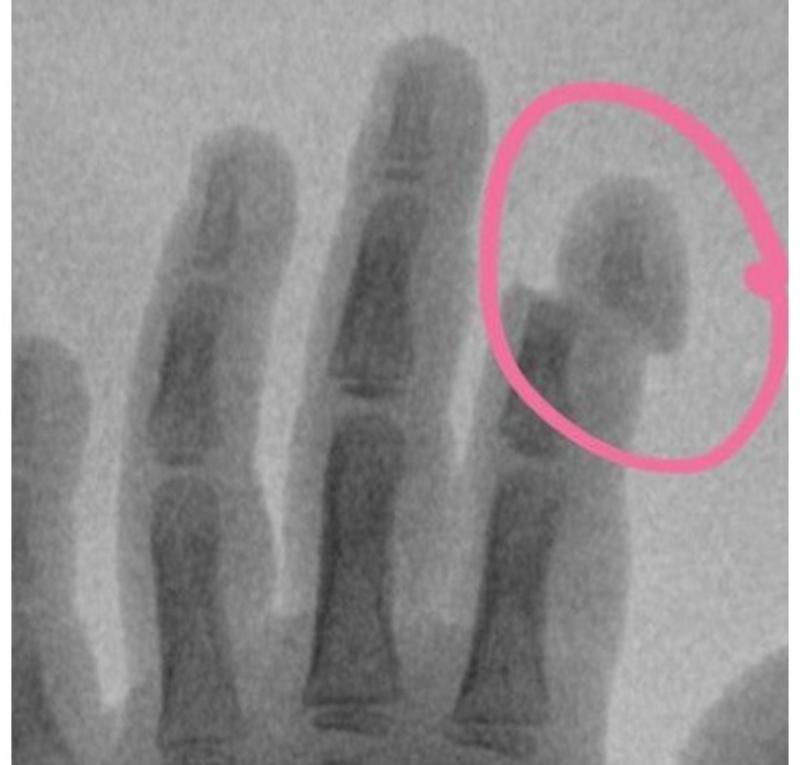

5-летняя девочка поступила с травмой указательного пальца в Московскую областную детскую клиническую травматолого-ортопедическую больницу (МОДКТОБ): ногтевая фаланга буквально держалась за счет кожи. Как выяснилось, травму маленькая пациентка получила из-за детской коляски, ее механизм буквально «отщелкнул» палец, сообщает пресс-служба регионального Минздрава.

«Специалистами больницы проведены ревизия раны, артропластика – хирургическая процедура, необходимая для восстановления функции сустава. Кроме того, была проведена пластика сухожилия разгибателя и восстановлены сосуды. Данная травма крайне тяжелая и сопряжена с длительным реабилитационным периодом. Конечный результат операции и объем восстановления после травмы будет виден нескоро, поэтому пока все зависит от организма ребенка и его способности к восстановлению. К счастью, детский организм имеет неисчерпаемые возможности и способен к регенерации», - рассказал Григорьев Александр Владимирович главврач медучреждения и главный внештатный детский специалист травматолог-ортопед Минздрава Московской области.